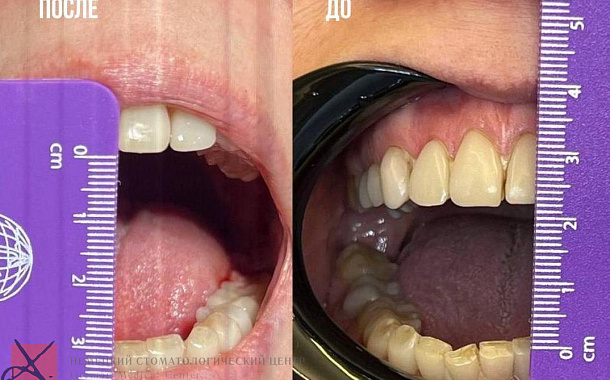

Полный прайс-листКейсы: до и после

Уже на этапе диагностики и планирования лечения зубов мы можем с 99% точностью показать пациенту, как будут выглядеть его зубы после лечения в Немецком Стоматологическом Центре. Наш пациент всегда четко понимает, как будет закрываться его челюсть, как будут выглядеть его зубы, улыбка и лицо после лечения зубов. От нас пациент всегда уходит полностью удовлетворенный лечением и получает именно тот результат, который мы ему показали на первой встрече.